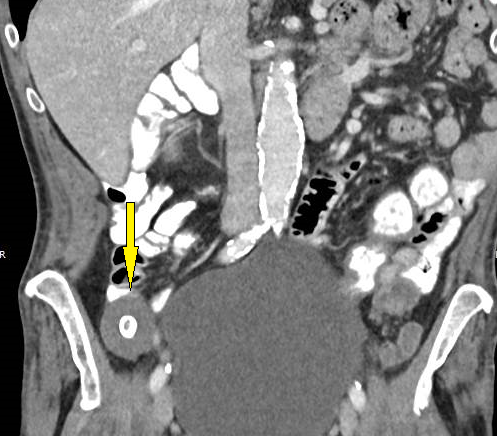

Flowchart eFTR bei Patienten mit rNET